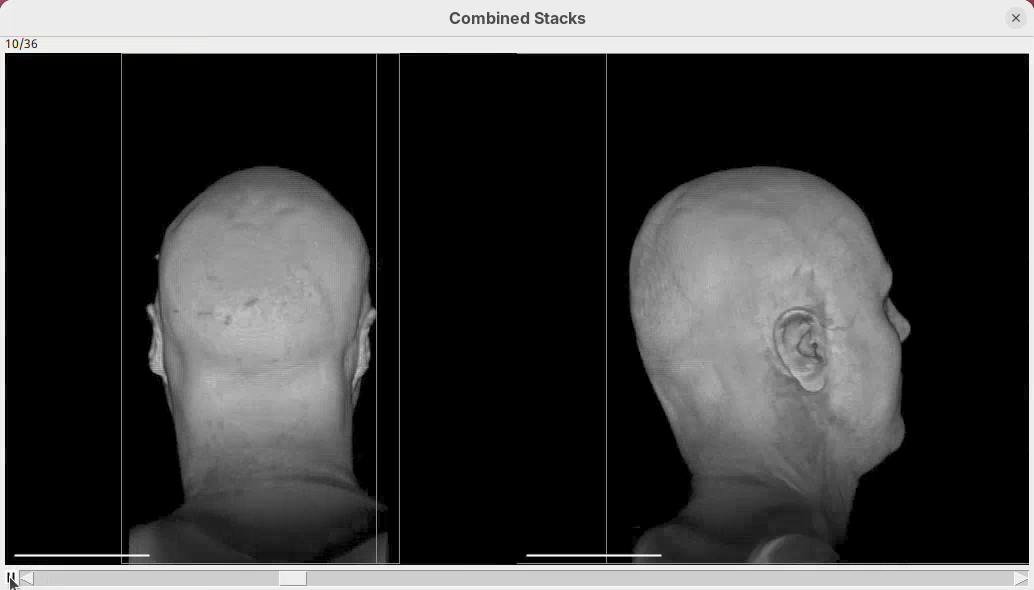

Animate cropping

Let’s add a couple more commands below our rotation sentence. We want that, after the 360 degree rotation, the animation slices through the head to show the tissues inside. For that, we can change the cropping parameters to control the position of the bounding box during the animation.

- After the first sentence, write the two commands as shown below:

From frame 0 to frame 35 rotate by 360 degrees horizontally

From frame 36 to frame 71 change channel 1 bounding box min z to 60

From frame 72 to frame 99 change channel 1 bounding box min z to 0- Press

Run.

The script is saying to rotate 360 degrees horizontally, as before, set the Z range minimum to 60 (roughly halfway through the sample) for about 30 frames, and then set the Z range minimum back to 0 in the subsequent 30 frames. And that’s what we get.